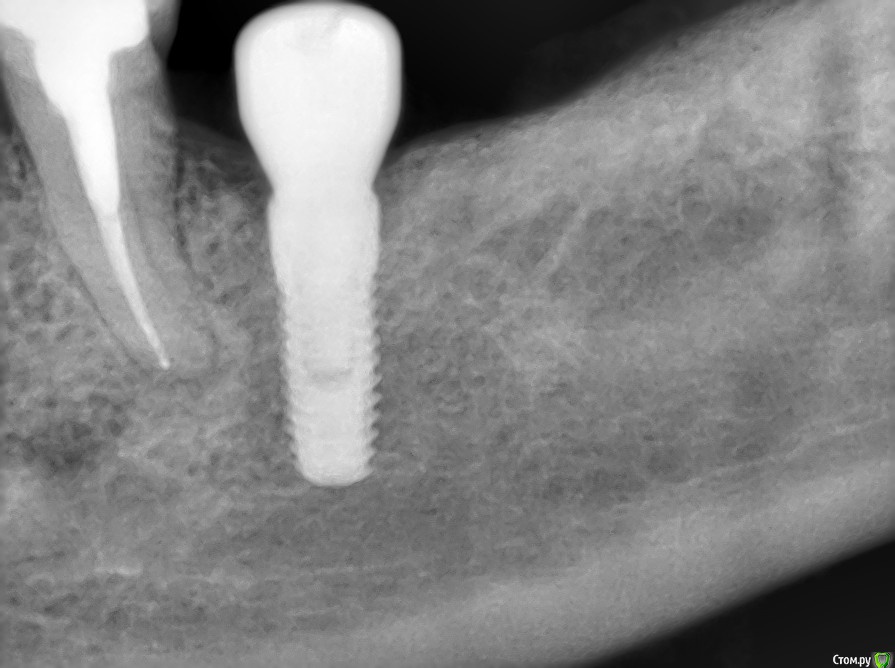

kriokov Опубликовано 1 апреля, 2017 Поделиться Опубликовано 1 апреля, 2017 Ревматоидный и метатрексат.(тоже просил помощи у коллег) Болт в обл 36, суперлайн. фото с коронкой полгода назад ортопед сделалМне кажется свищи, это имплантат коронально "голый ", и слизистая тонкая, хотя всегда возможны другие факторы. 1 Ссылка на комментарий